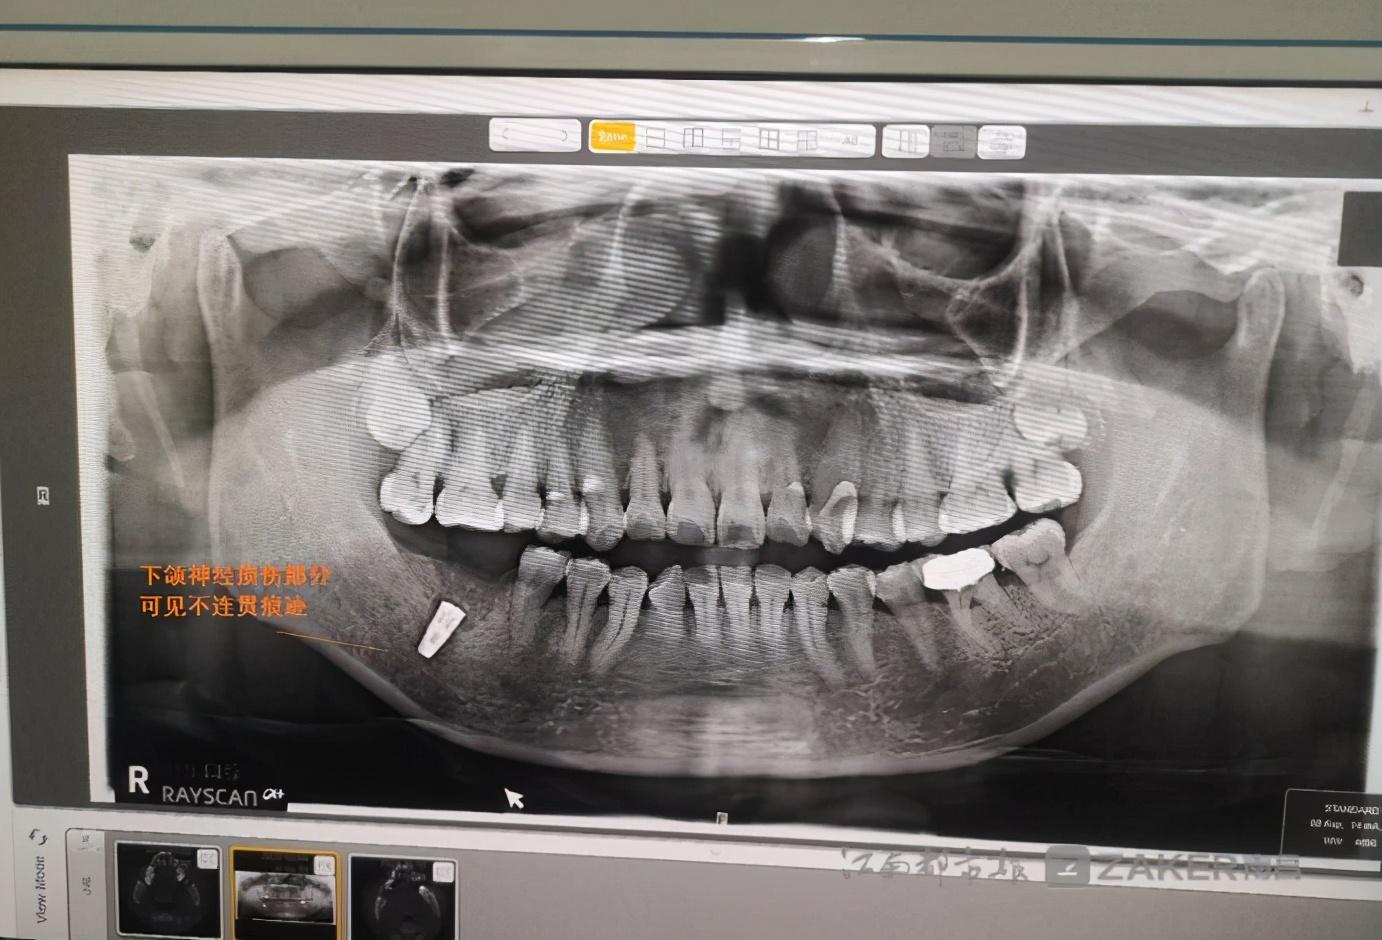

消炎針打完后,下頜的麻木感仍然存在。在家人的陪同下,繆女士前往專業(yè)口腔醫(yī)院檢查。在一份由南昌大學附屬口腔醫(yī)院 9 月 29 日出具的診斷證示,"46 牙可見種植體植入影像,下頜神經(jīng)管上壁可見不連續(xù)影像。" 繆女士告訴記者,經(jīng)檢查診斷后得知,自己的下頜神經(jīng)因種植牙手術(shù)受到損傷,這是下頜麻木的根本原因。